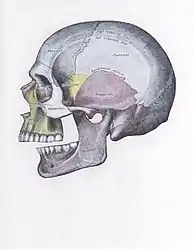

- Side view of the skull with posterior dislocation of jaw.

There are four different positions of jaw dislocation: posterior, anterior, superior and lateral. The most common position is anterior, while the other types are rare. Anterior dislocation shifts the lower jaw forward if the mouth excessively opens. This type of dislocation may happen bilaterally or unilaterally after yawning. The muscles that are affected during anterior jaw dislocation are the masseter and temporalis which pull up on the mandible and the lateral pterygoid which relaxes the mandibular condyle. The condyle can get locked in front of the articular eminence. Posterior dislocation is possible for people who get injured by being punched in the chin. This dislocation will push the jaw back affecting the alignment of the mandibular condyle and mastoid. The external auditory canal may be fractured. Superior dislocations occur after being punched below the mandibular ramus as the mouth remains half-open. Since great force occurs in a punch, the angle of the jaw will be forced upward moving towards the condylar head. This can result in a fracture of the glenoid fossa and displacement of the condyle into the middle cranial fossa, potentially injuring the facial and vestibulocochlear nerves and the temporal lobe. Lateral dislocations move the mandibular condyle away from the skull and are likely to happen together with jaw fractures.[4][5]

The joint involved with jaw dislocation is the temporomandibular joint (TMJ). This joint is located where the mandibular condyles and the temporal bone meet.[4][6] Membranes that surround the bones help during the hinging and gliding of jaw movement. For the mouth to close it requires the following muscles: the masseter, temporalis, and medial pterygoid muscle. For the jaw to open it requires the lateral pterygoid muscle.[4]